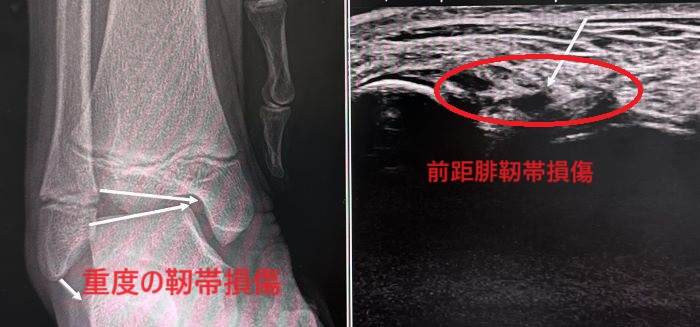

診断はレントゲン検査と超音波検査です。レントゲンではケガをした時の足首の状態を再現したストレスレントゲン撮影が診断に有益です(断裂例)。また、超音波検査は動的に損傷部を観察できるため有益な情報を与えてくれます。

脛腓靭帯損傷、外側側副靭帯損傷、内側側副靭帯損傷などがあるタイプです。

大半は内反が強制されて起こる外側側副靭帯損傷で、特に強度の弱い距腓靭帯損傷をよく見かけます。